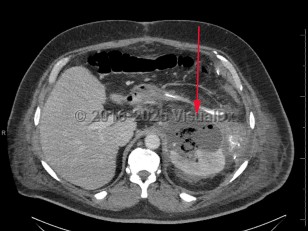

Perinephric abscess

Perinephric abscesses can be the consequence of pyonephrosis due to an obstruction nephrolith, recurrent pyelonephritis, or the rupture of a corticomedullary intra-nephric abscess. Perinephric abscess can also result from the spread of infection from extraperitoneal sites via hematogenous dissemination or from infection from adjacent structures such as the bowel, pancreas, and spine.

The clinical presentation is usually characterized by the insidious onset of fever, flank or abdominal pain, fatigue, and weight loss. Physical findings include flank or costovertebral tenderness. A palpable mass may be present in some cases.